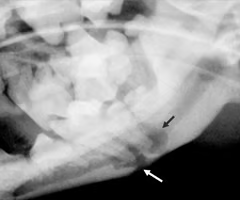

Identify the pathology?

Extradural